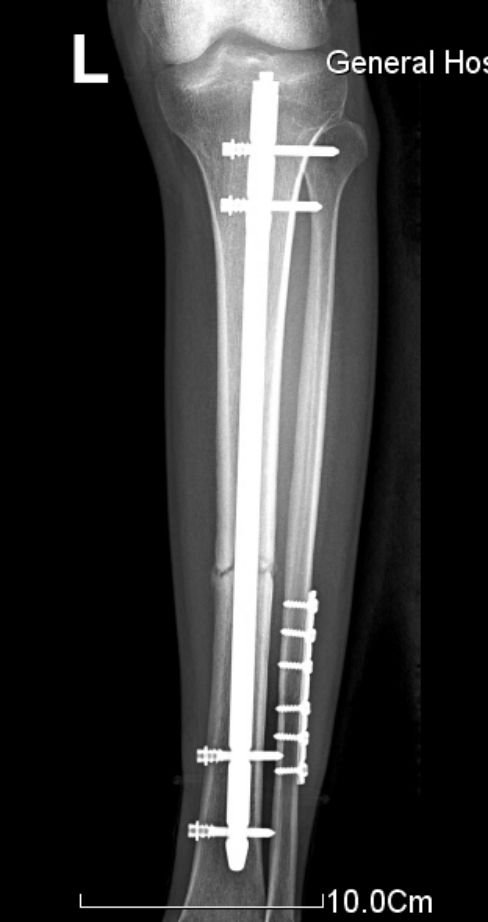

交锁髓内钉有较好的抗旋转、抗压缩作用,固定稳定性好,符合生物学固定原则(BO),在四肢长骨中应用广泛。

固定骨折的力臂比钢板长,作用力均匀分散在整个骨干的中轴上,不易发生折弯变形。

锁钉使骨干从上到下形成一体,防止缩短和旋转,对骨折的固定达到最大的稳定性。

胫骨中1/3稳定型骨折:横形骨折、短斜形骨折、假关节。

胫骨中部60%长度内的不稳定性骨折:干骺端附近的骨折、长螺旋形骨折、节段性骨折、粉碎性骨折、骨折伴骨缺损。

多用于胫骨中段骨折。尽管也可用于胫骨近端和远端骨折,但并发症发生率较高,易发生畸形愈合。